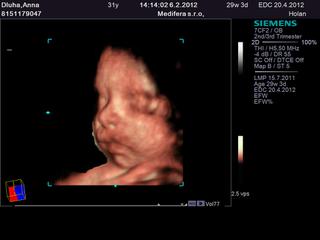

jóój baby ja vám tak závidím tie 4D fotky a videa ☹ ja mám poslednú zo 16tt v 2D